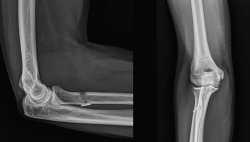

En cuanto a las pruebas de imagen, las radiografías simples suelen ser normales en todas las lesiones del bíceps distal y no añaden información más allá de cambios discretos por reacción perióstica en la tuberosidad bicipital y, en casos muy poco frecuentes, avulsión de un fragmento óseo(19).